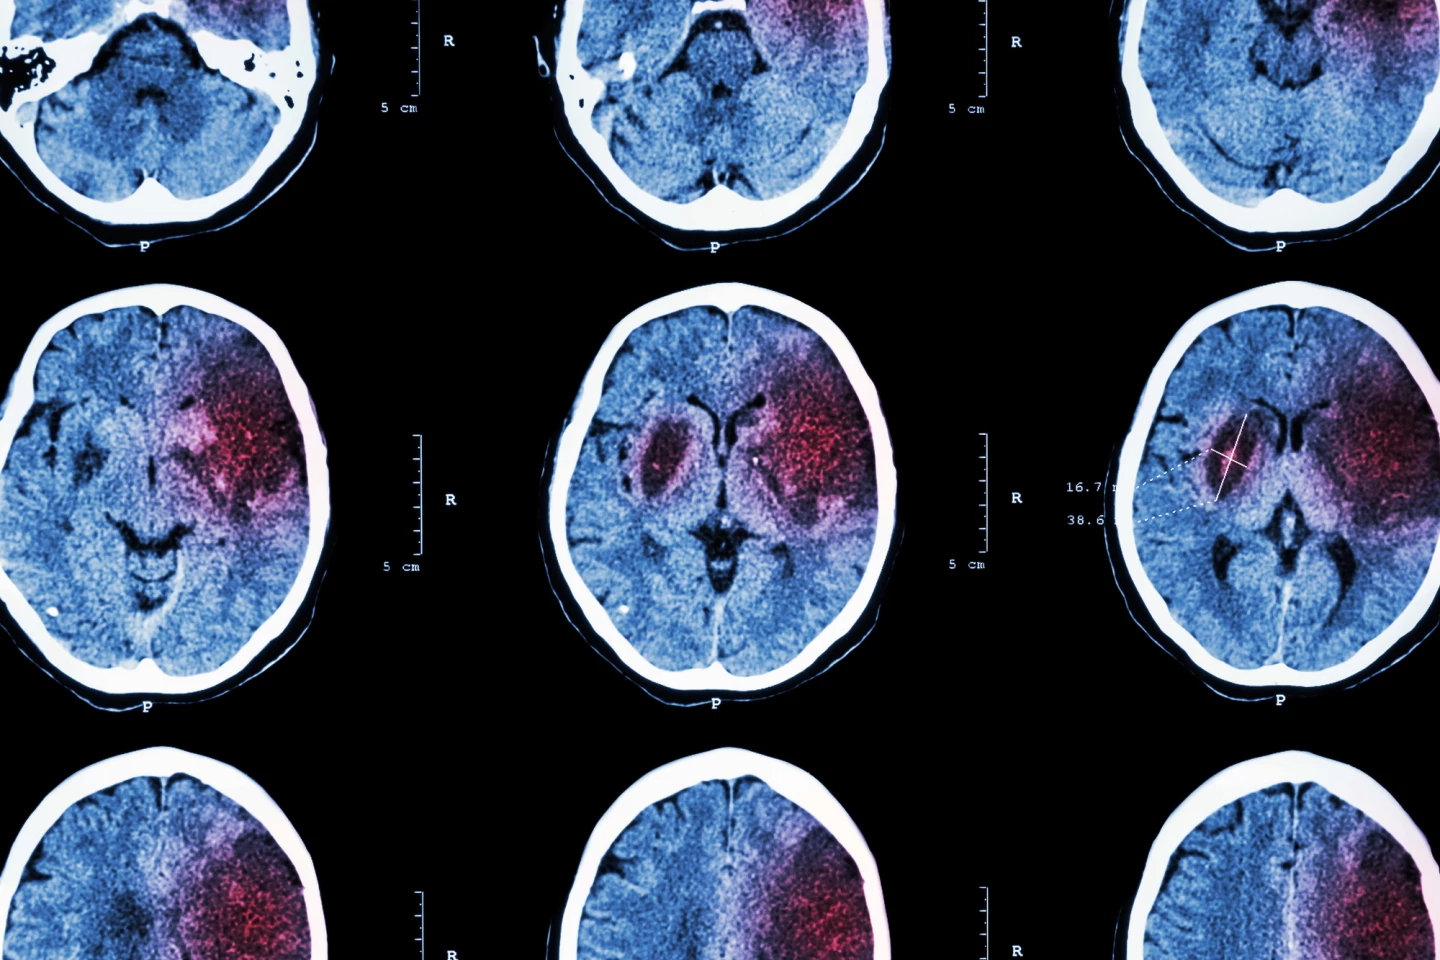

Worldwide, one in four over 25s will have a stroke in their lifetime. The sudden symptoms indicating that someone’s had a stroke are well-recognized and are treated by intensive physical and occupational therapy. However, the long-term effects of stroke – cognitive impairment and depression resulting from damage to the brain’s cells or neurons, for example – can be harder to treat. But a new study by researchers at Texas A&M University has capitalized on the gut-brain link to protect the brain from the long-term ravages of stroke using a naturally occurring hormone.

“Stroke is one of the leading causes of dementia and AD [Alzheimer’s disease],” said Dr Farida Sohrabji, Head of the University’s Department of Neuroscience and Experimental Therapeutics and the study’s corresponding author. “While there are acute, immediate consequences of stroke, there are also these long-term consequences that affect quality of life for the patient as well as the caregivers, so there’s a lot of interest in understanding how to improve long-term outcomes.”